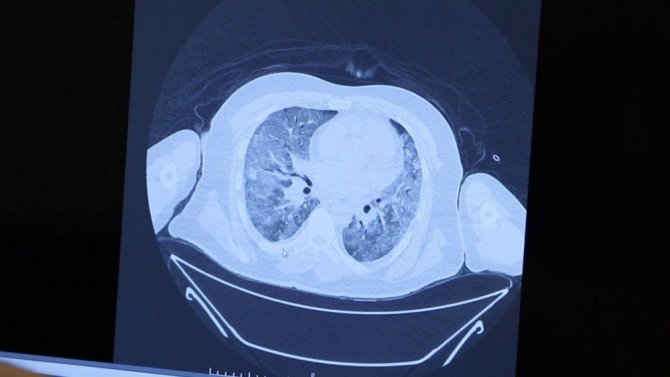

Korona geçirmiş bir ailenin akciğer tomografilerini inceleyen Prof. Dr. Özkaya, "Bir örnek vermek gerekirse, bu genç hastamız 26 yaşında, ailede ilk kez bu çocuk pozitif oluyor. Genç olduğu için hafif atlatıyor. Sonra annesini enfekte ediyor. Annesi çocuktan bir tık daha fazla akciğer tutulumuyla geliyor. Daha sonra da babası enfekte oluyor. Annesini tedavi ettik ama babası inanılmaz solunum yetmezliğiyle bize başvurdu. Yani virüs "akıllı bir organizma" gibi davranıyor. Ailede birini enfekte ettiği zaman diğer enfekte edeceği kişide bir tık daha kötü akciğer hasarı yapıyor. Bu konuda vatandaşlarımızın mutlaka aile içindeki temasa çok dikkat etmesi lazım. Virüs 2019'da bulundu, 2020'de salgın ilan edildi, hastalığın 2021'de daha kötü bir tabloya yol açmaması için herkesin dikkat etmesini ve aşı konusunda da duyarlı olmasını istiyoruz. Çünkü tek kurtuluşumuz şu an aşı gibi duruyor" şeklinde konuştu.